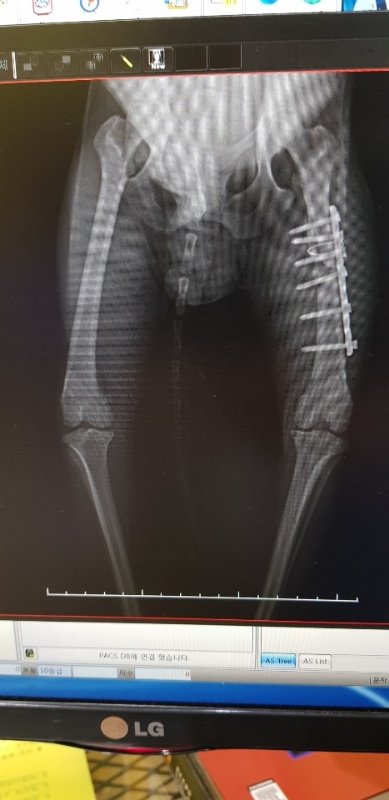

교통사고로 다리 수술했어요

골절수술 무사히 잘 받았습니다.

다행히 수술은 아주 잘 됐다고 하시네요

앞으로 수술경과도 지켜봐야하고 사상충치료도 해야합니다

6.8키로 남아 중성화완료

다리골절수술완료 사상충치료중